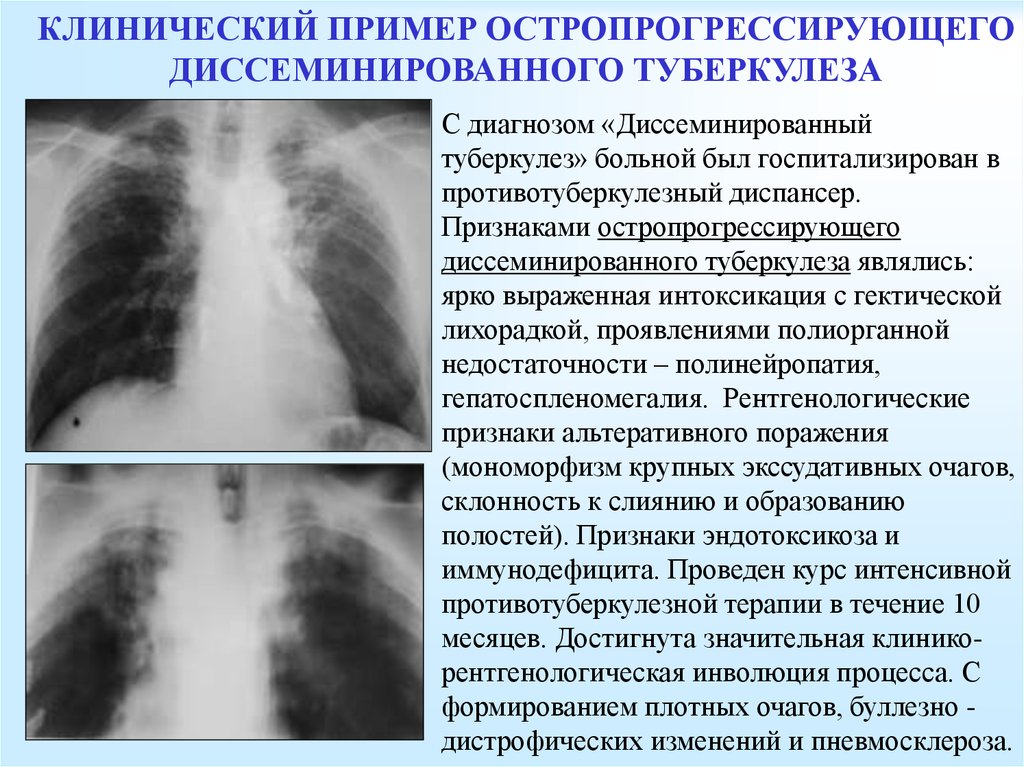

В клинической картине острого гематогенно диссеминированного туберкулеза преобладает